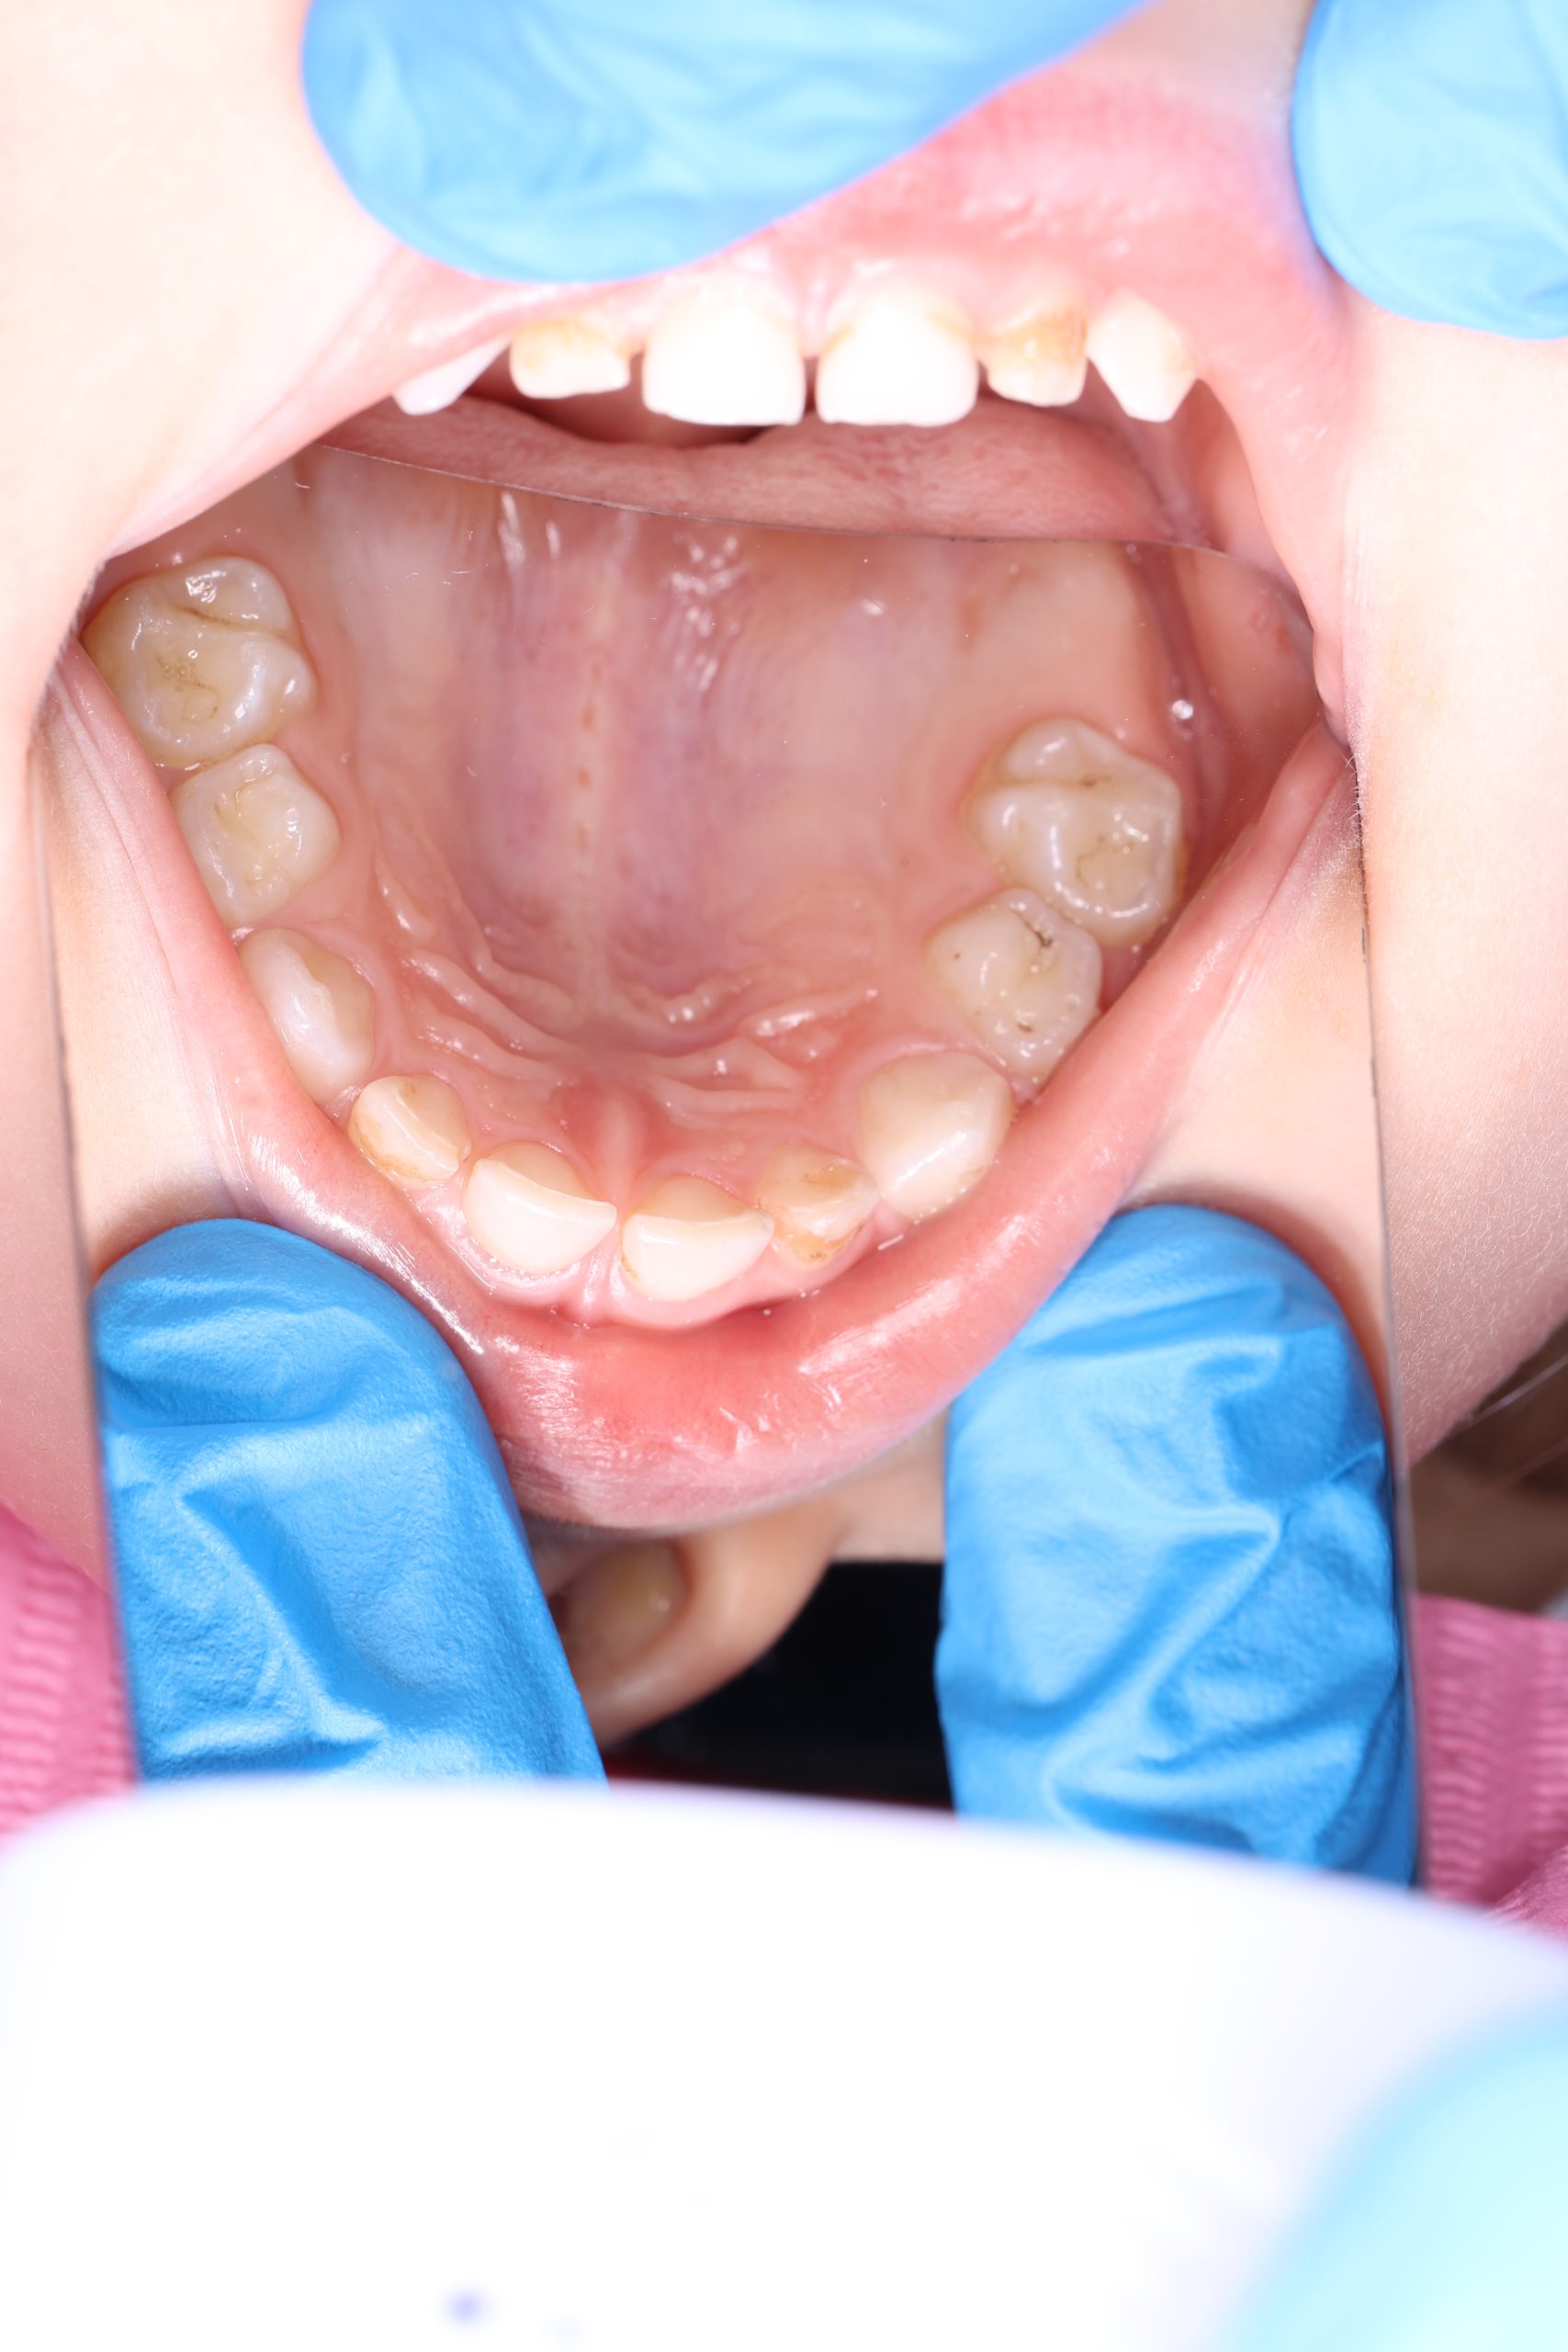

We examine the condition of teeth, gums, and bite. - Plaque Disclosure with Special Indicators

Areas that weren’t cleaned well appear purple. The darker the shade, the older the plaque. This helps both kids and parents understand where brushing needs to improve. - Brushing Training & Home Care Tools Selection